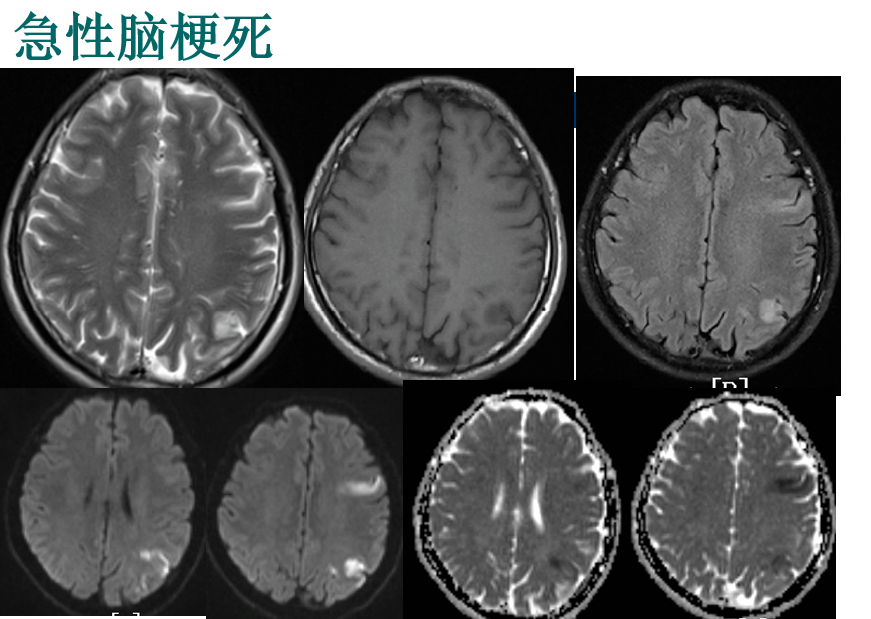

磁共振,英文名叫MRI,是目前临床上常见的影像学检查手段。它的原理是检查时人体置身于在磁场环境中,利用人体内氢质子含量的不同进行成像。

磁共振检查没有创伤、没有辐射,软组织分辨率高、图像清晰,可帮助医生“看见”不易察觉的早期病变,被广泛应用于颅脑,心脏,大血管,胸腹,四肢关节等多种临床病变的诊断。

颅脑核磁:适用于脑部各类疾病的检查如:头疼、眩晕、脑供血不足等、脑梗塞及脑出血的早期检查,脑梗塞、脑出血的康复期复查、颅脑占位的检查等。颅脑核磁检查还包括副鼻窦、脑垂体、眼眶、内耳的检查申请时请特别注明。

颅脑血管核磁:适用于脑部血管病变的检查如:颅脑血管畸形、脑供血不足、脑梗塞及脑出血后的血管改变等。